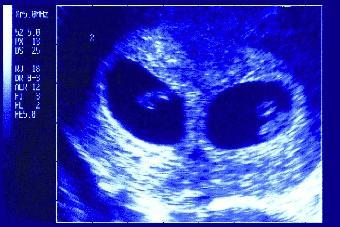

S'intéressant à l'humain, Virpi Lummaa (Turku, Finlande) et coll. se sont demandé si, au cours d'une grossesse gémellaire comportant un garçon et une fille, celle-ci est soumise à l'influence de la testostérone de son frère. En revanche, ce dernier ne peut être influencé par les estrogènes de sa soeur, car leurs taux sont similaires.

Les chercheurs se sont intéressés à la santé et à la fécondité ultérieures de ces femmes. L'équipe a remonté le temps afin d'éliminer les biais dus à la contraception et aux progrès réalisés en matière de santé. Ils ont analysé les grossesses gémellaires recensées dans cinq paroisses rurales de Finlande entre 1734 et 1888, soit 754 grossesses (6 fois plus de naissances de jumeaux dizygotes que monozygotes).